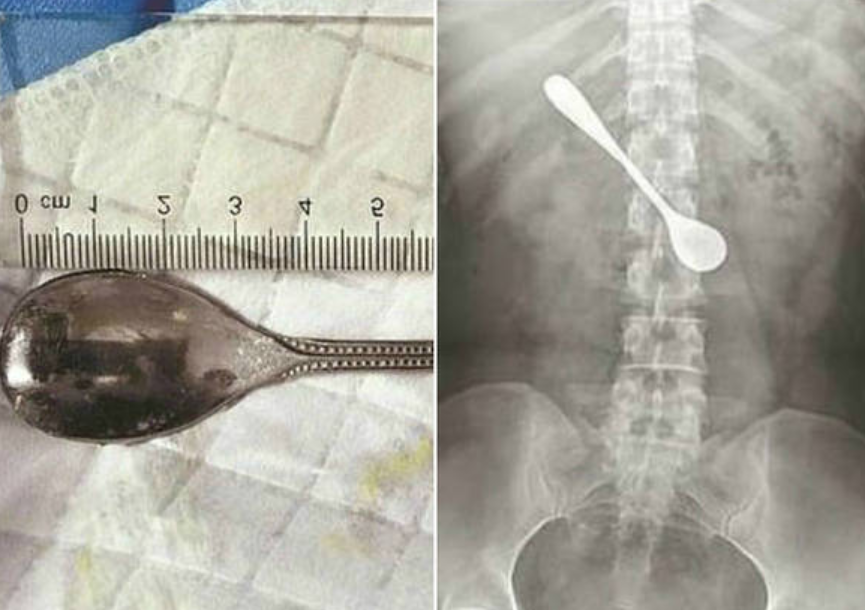

Um mulher passou quatro dias com uma colher alojada no intestino, segundo o R7. Ela tentava retirar una espinha quando engoliu o objeto mecânico de 13 cm. Ela não procurou auxílio médico imediato por achar difícil ser atendida durante um festival local.

"Como a colher estava em uma posição horizontal, nós a ajustamos cuidadosamente antes de puxá-la verticalmente", explicou o médico Sun Tingji,